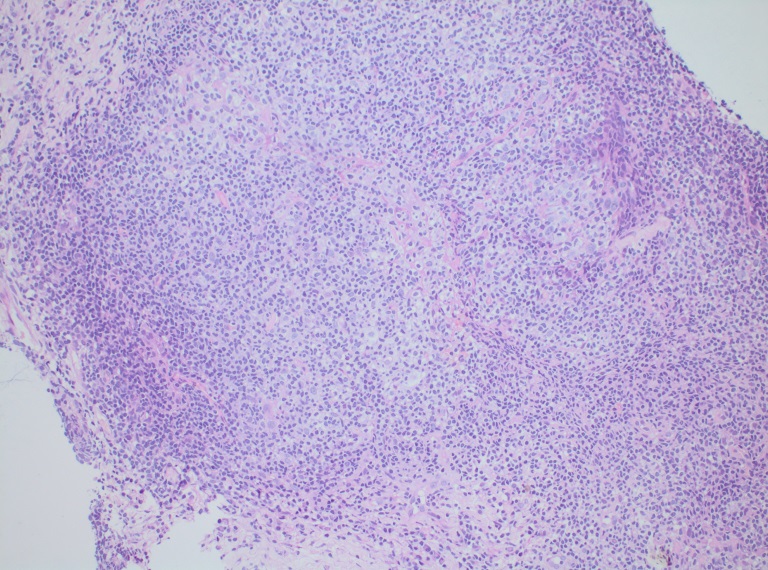

Существуют объективные трудности клинической и морфологической диагностики опухолей средостения, особенно лимфоидной природы. Получить диагностический материал сложно, для этого используют различные виды биопсий, но полученный материал зачастую небольшого объема и деформирован. Помимо малого количества и деформации материала, что само по себе затрудняет морфологическую диагностику, лимфомы средостения демонстрируют значительную вариабельность гистологических и цитологических изменений, что влечет за собой необходимость выполнения иммуногистохимического исследования во всех случаях (рис.8,9).